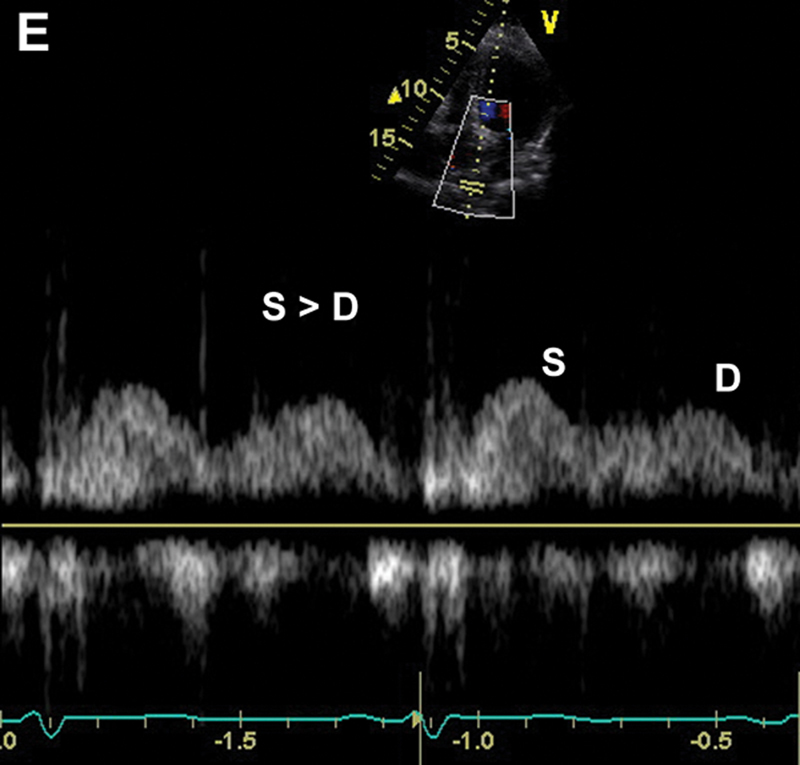

فحوصات تشخيصية لبعض امراض القلب والشرايين التاجية